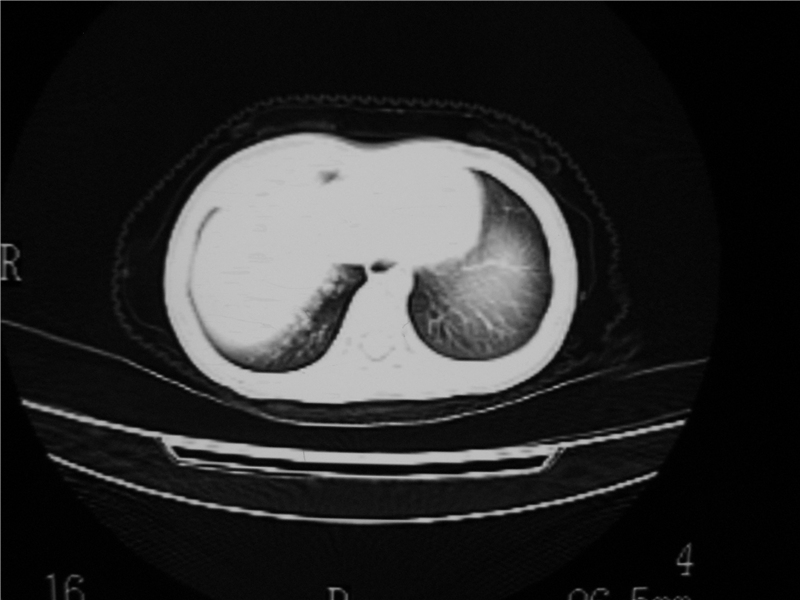

标题: PED3236:男2岁进食花生米后发烧10天。

右肺中叶及下叶内段大片实变密度增高影,可见支气管气象,肺炎.

摄吸气及呼气相对比片,本例为有肺中叶阻塞性炎症、不张,右肺下叶阻塞性炎症。

1)右肺炎症并右肺中叶肺不张,右肺上叶充气不良。2)右侧支气管异物不排除。

结合临床考虑支气管异物并阻塞性肺炎、肺不张。